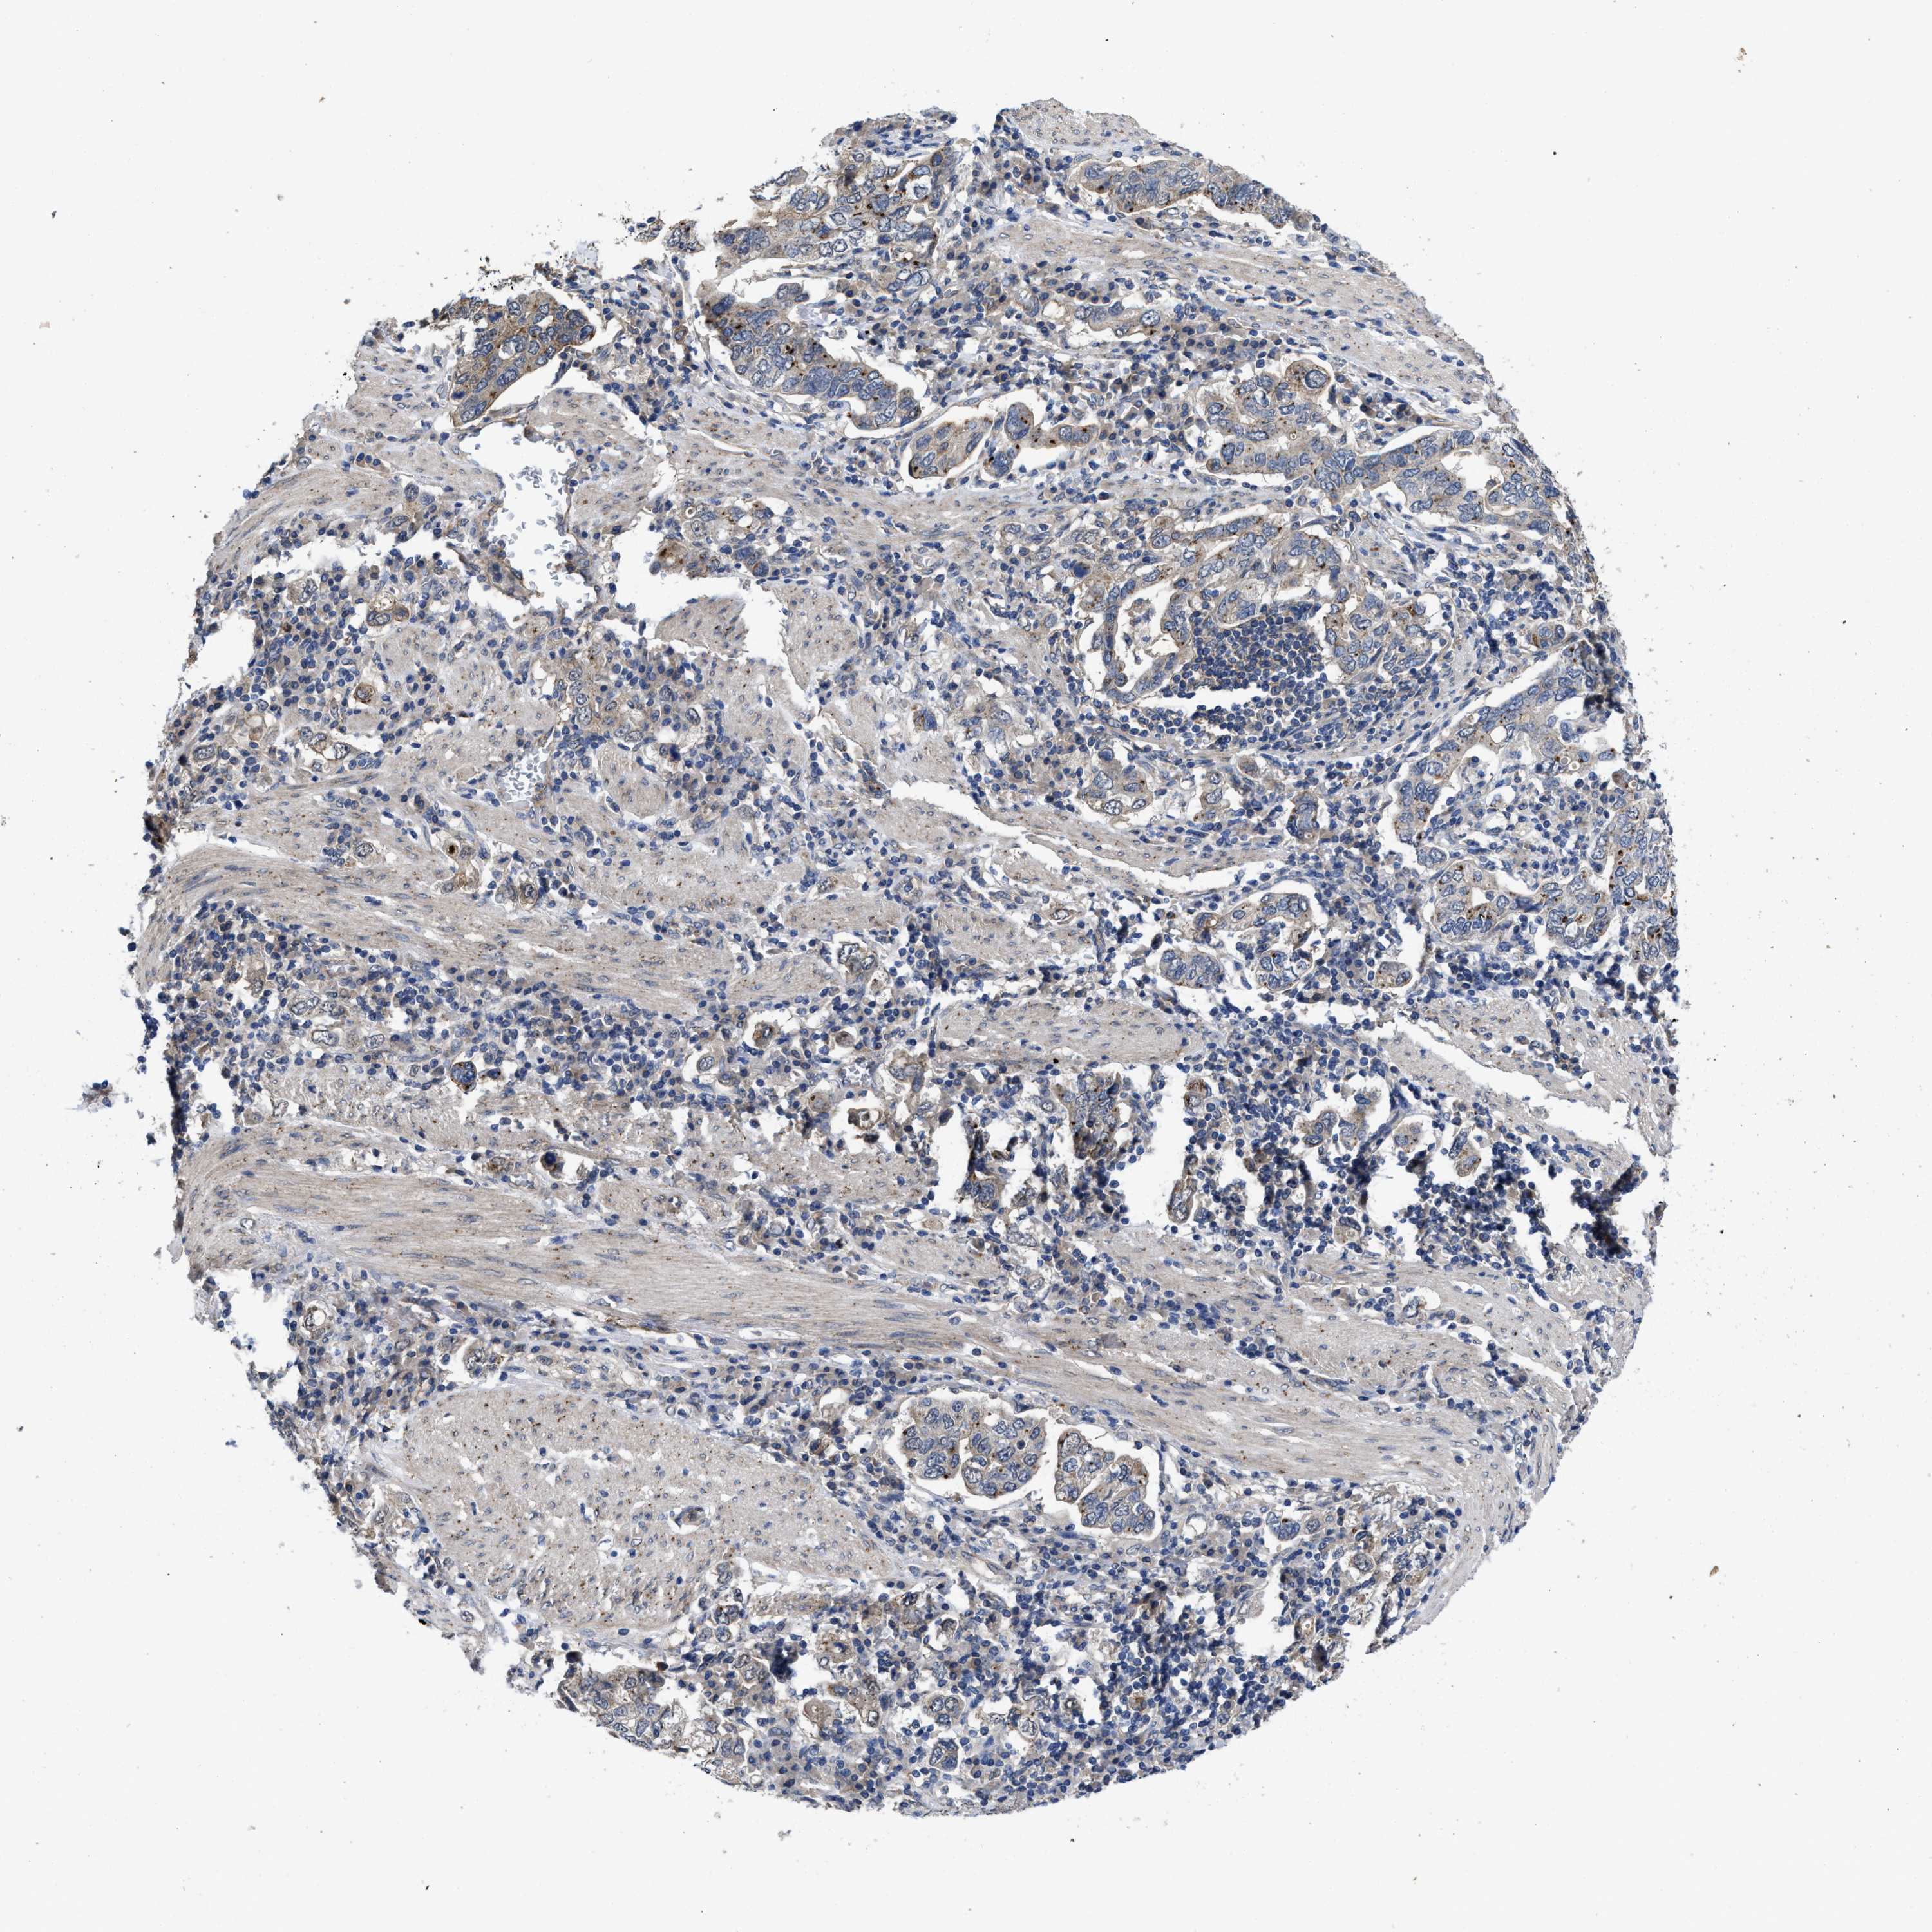

STOMACH CANCER - Protein expressioni

A mouse-over function shows sample information and annotation data. Click on an image to view it in a full screen mode. Samples can be filtered based on level of antibody staining by selecting one or several of the following categories: high, medium, low and not detected. The assay and annotation is described here.

Note that samples used for immunohistochemistry by the Human Protein Atlas do not correspond to samples in the TCGA dataset.

Antibody stainingi

Antibody staining in the annotated cell types in the current human tissue is reported as not detected, low, medium, or high, based on conventional immunohistochemistry profiling in selected tissues. This score is based on the combination of the staining intensity and fraction of stained cells.

Each image is clickable and will lead to virtual microscopy that enables deeper exploration of all samples and also displays staining intensity scores, fraction scores and subcellular localization as well as patient and tissue information for each sample.

Antibody HPA015794

Antibody CAB004544

Staining

High

Medium

Low

Not detected

Intensity

Strong

Moderate

Weak

Negative

Quantity

>75%

75%-25%

<25%

None

Location

Nuclear

Cytoplasmic/membranous

Cytoplasmic/membranous,nuclear

Adenocarcinoma, NOS

Adenocarcinoma, High grade